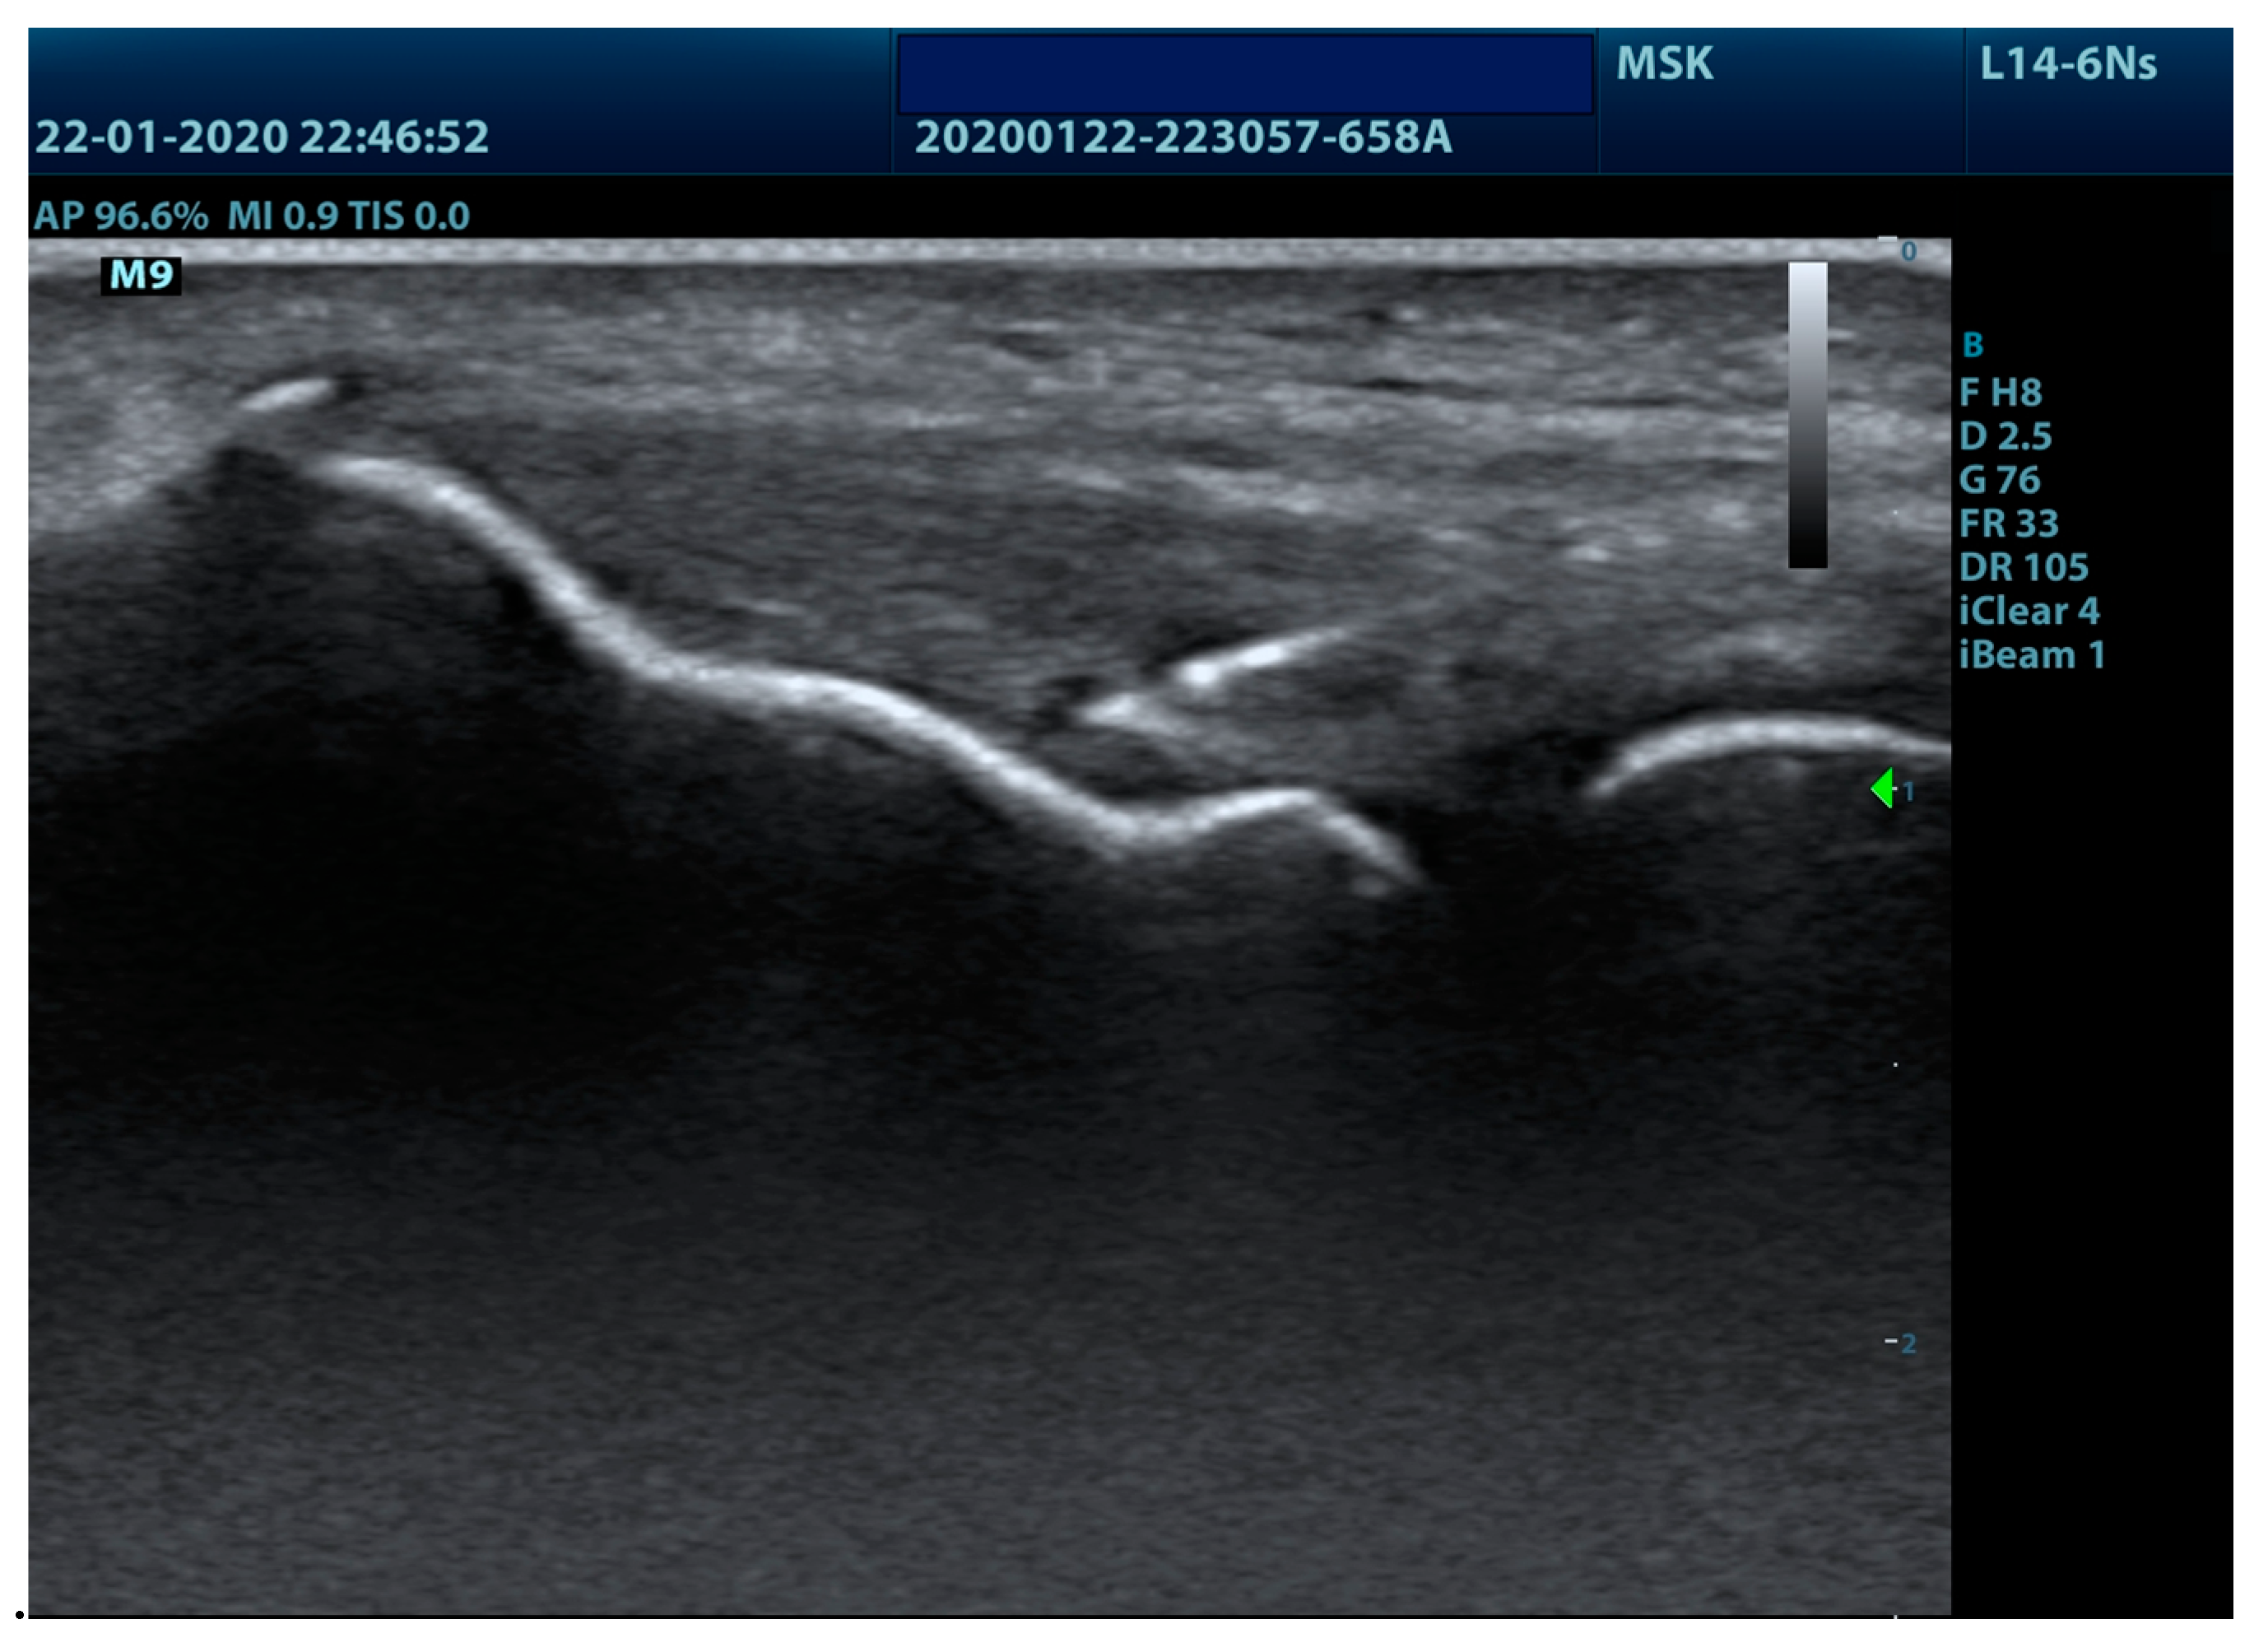

2.5.1. Experimental PE Group